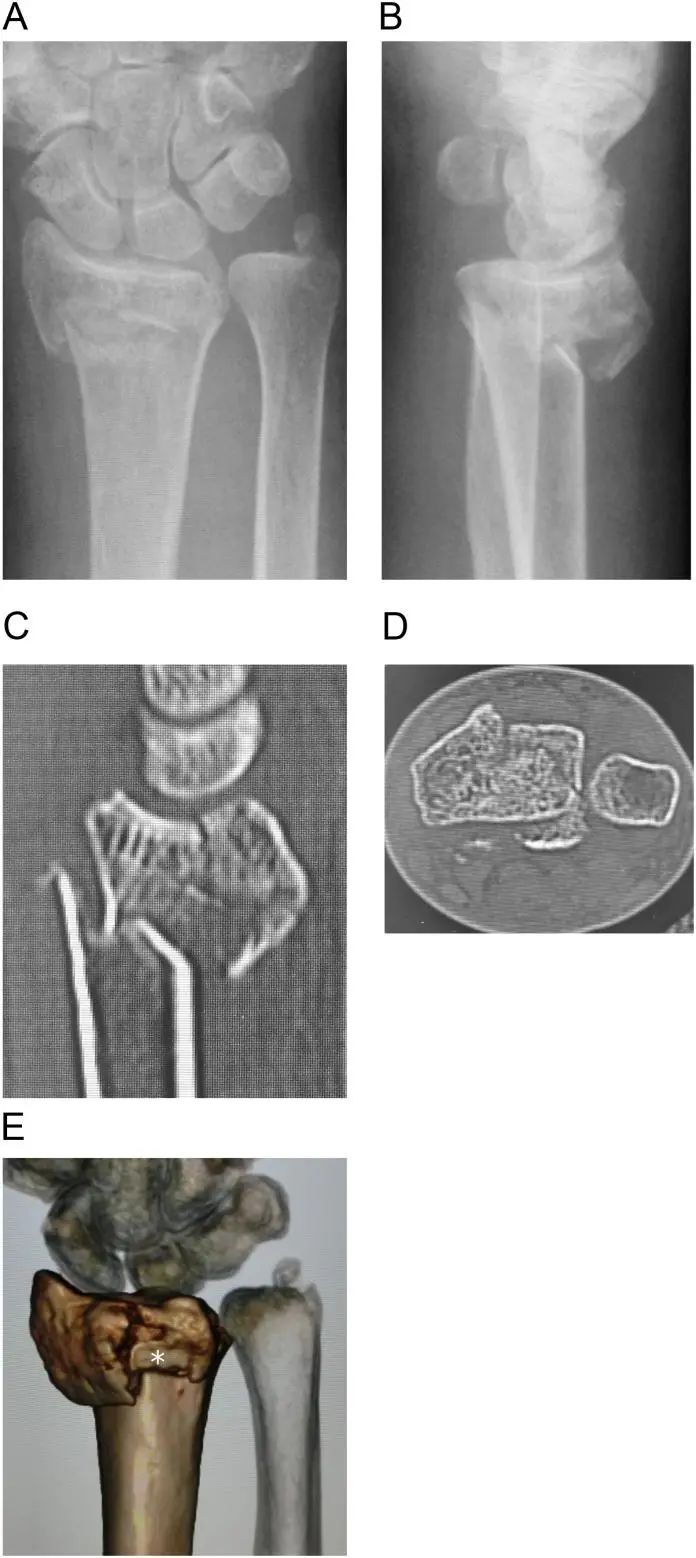

Случай был у 67-летней женщины с диагнозом внутрисуставной нестабильный перелом дистального отдела лучевой кости с правым дорсальным медиальным переломом (рис. 1A-E).Нет истории курения, диабета или употребления алкоголя.Может ходить без ходунков.

Рисунок 1. Предоперационная визуализация показала многооскольчатый внутрисуставной перелом дистального отдела лучевой кости.

A и B: предоперационные рентгеновские снимки,

C и D: сагиттальные и аксиальные проекции изображений компьютерной томографии,

E: 3D компьютерная томография.Видны дорсальные медиальные полулунные фасеточные фрагменты и дорсальные апикальные фрагменты (белые звездочки).